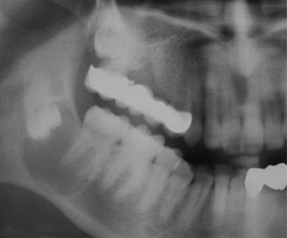

Impacted teeth